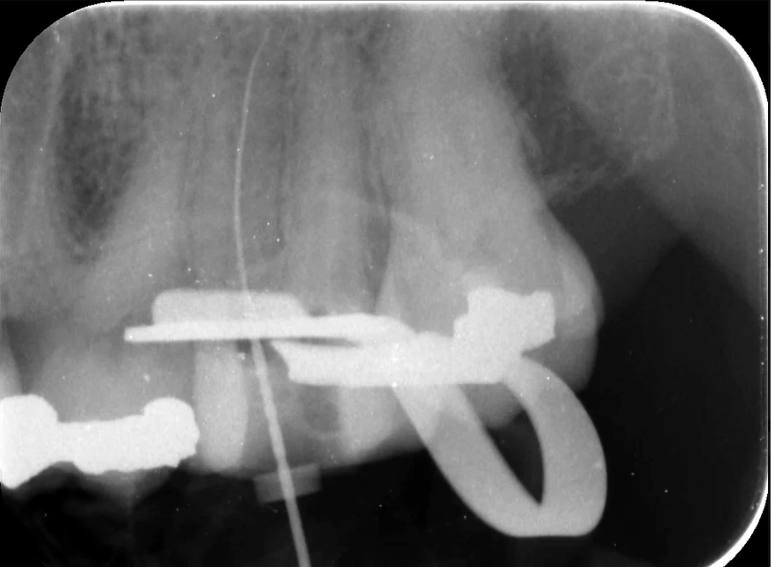

Root filling of a molar tooth.